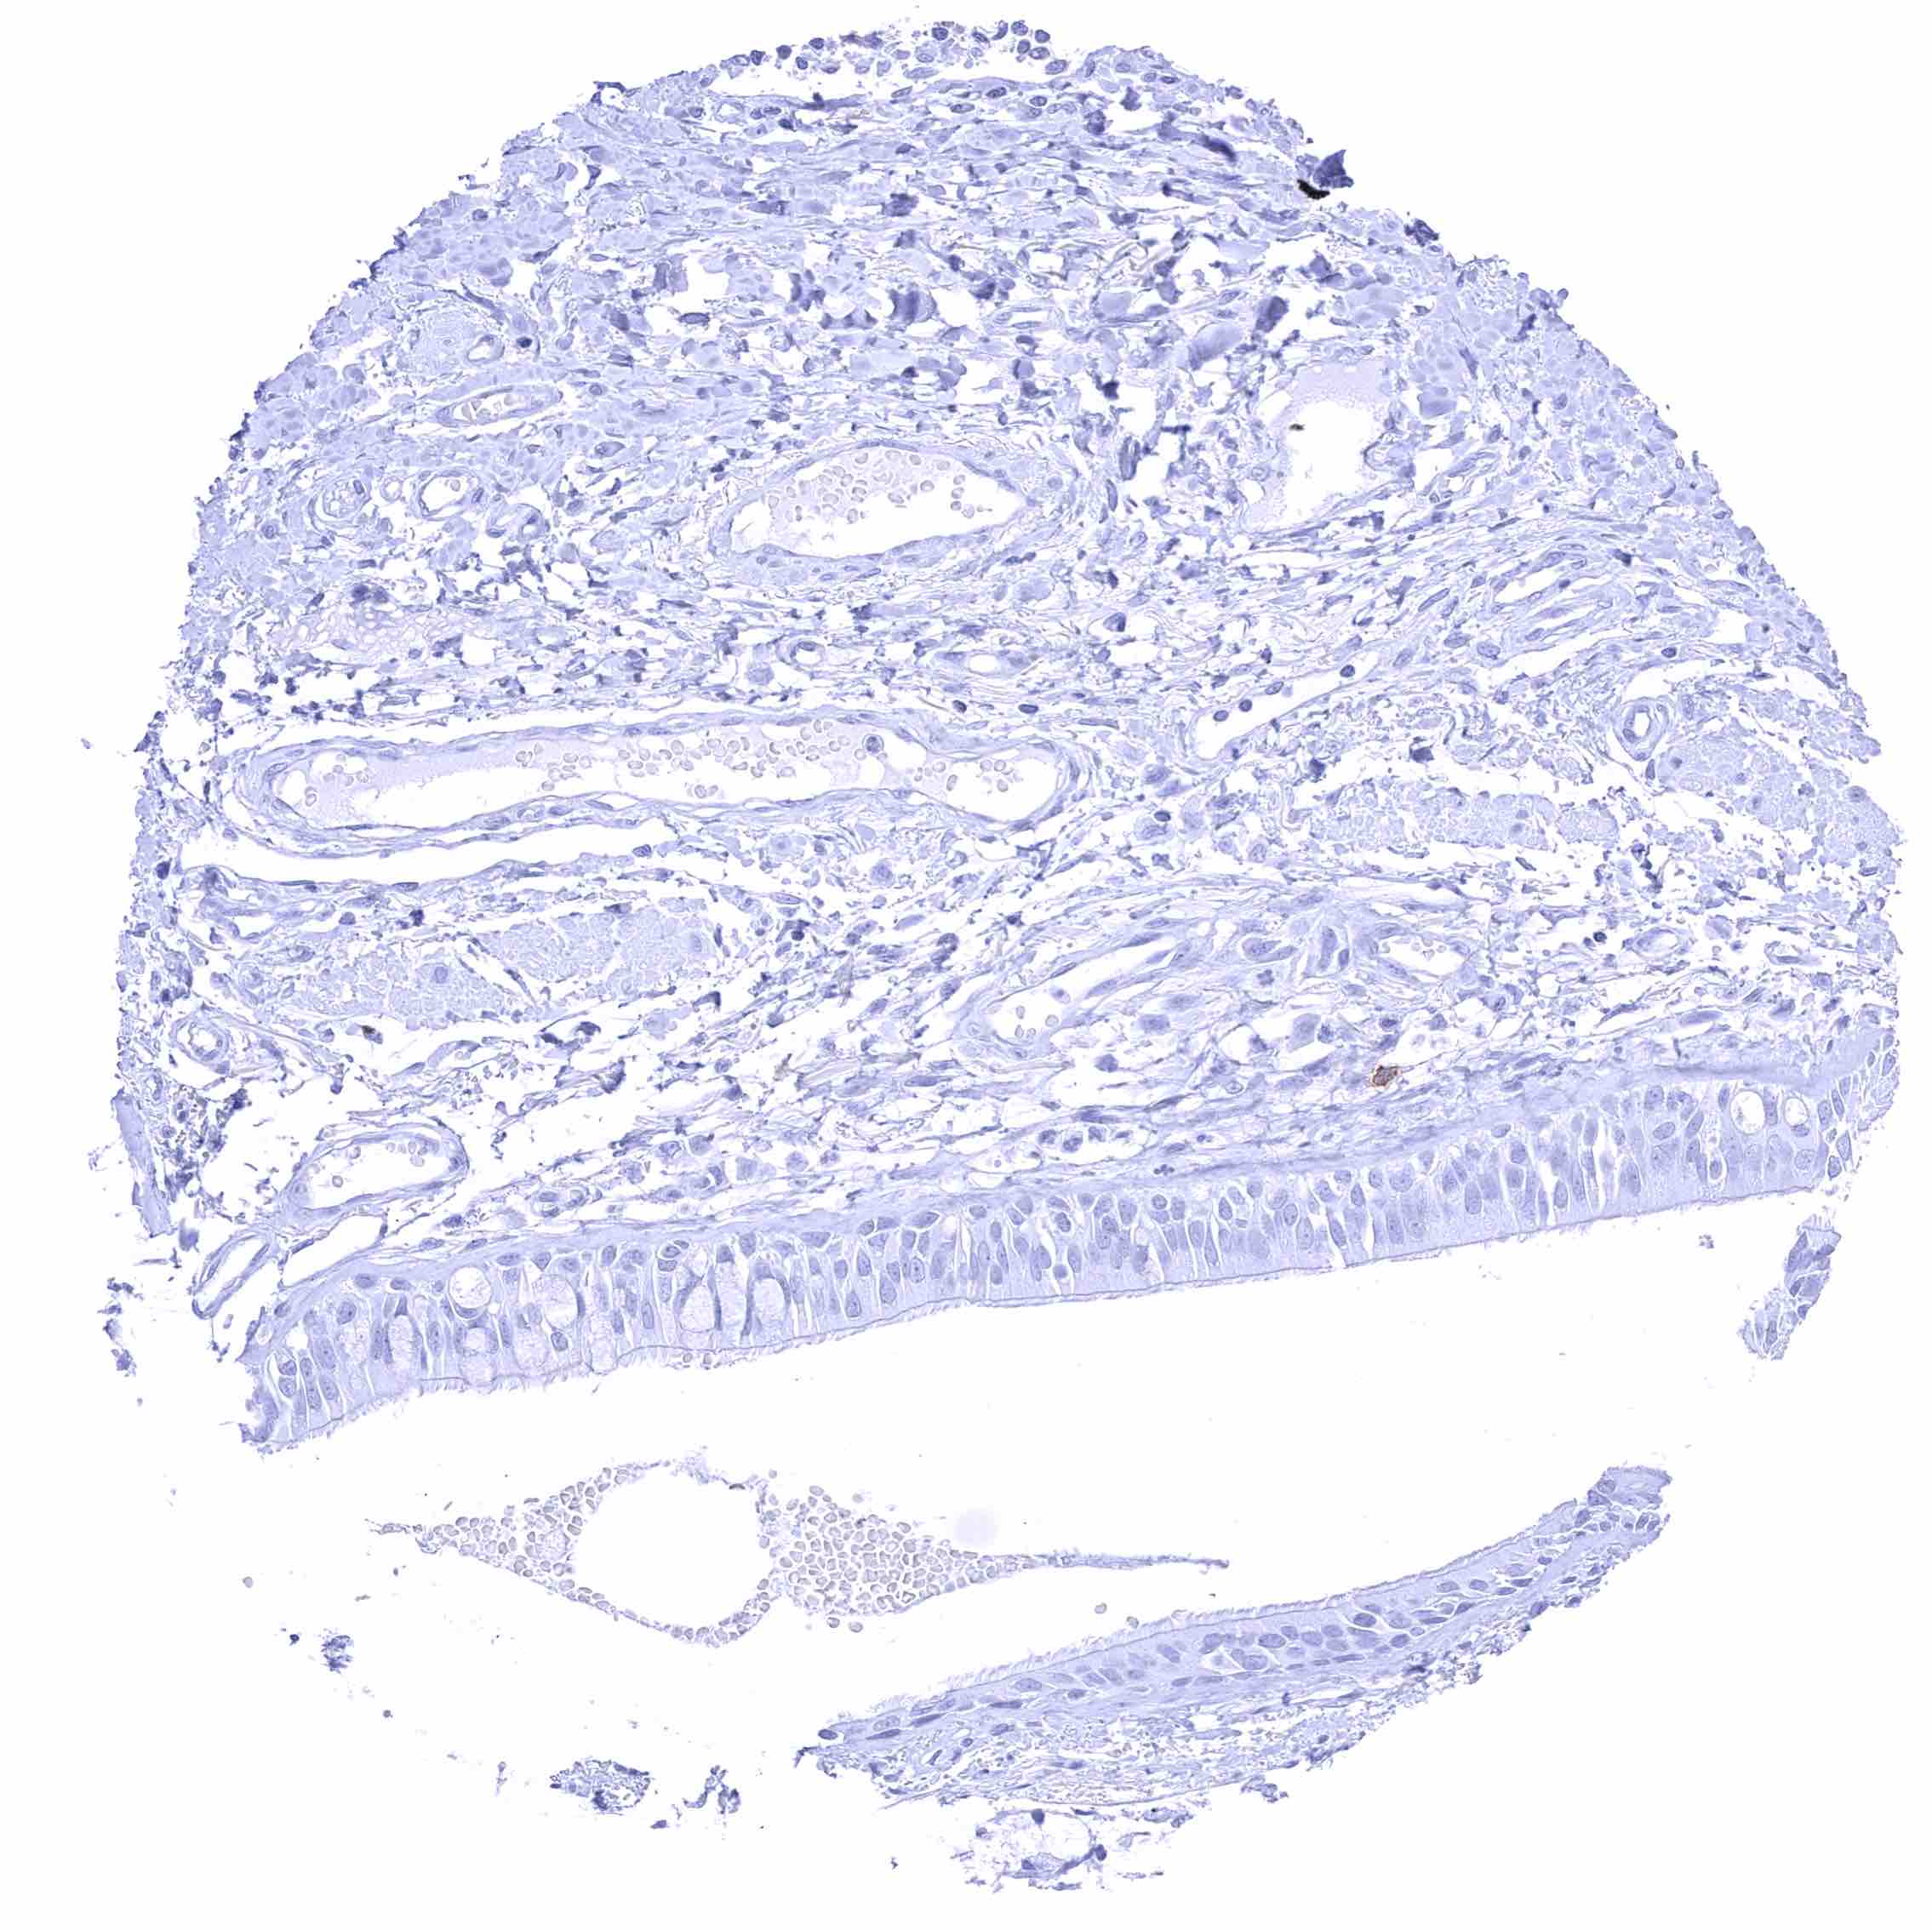

Appendix, mucosa – Epithelial cells are CD70 negative. Distinct CD70 positivity of a fraction of lymphocytic cells.

Appendix, muscular wall